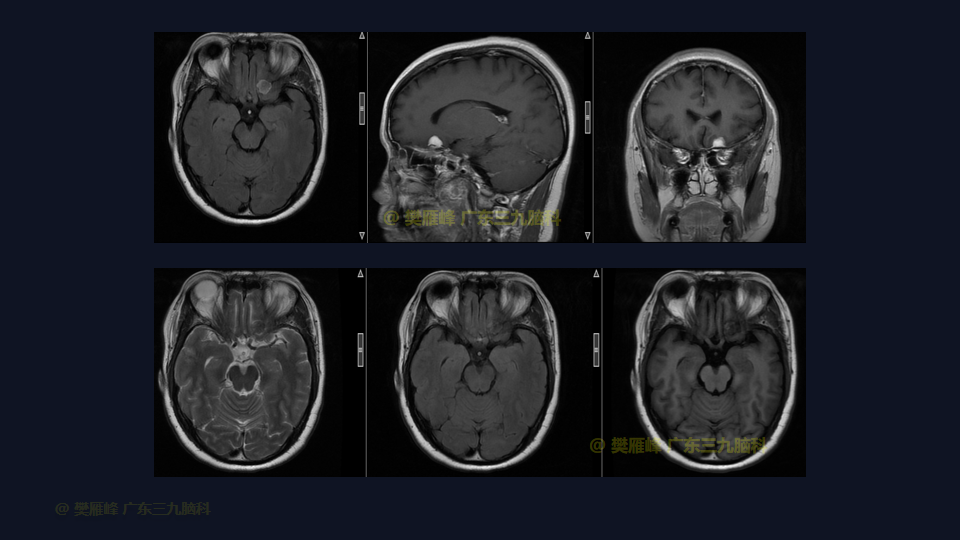

在这个二维手术视频中,展示了一种内镜经眶上锁孔入路微创切除嗅沟脑膜瘤的方法。患者是一名46岁的女性,有2年的头痛病史,近1周出现视物模糊,神经影像学显示左侧前颅窝底部示范围约12×16×10mm的均匀强化的嗅沟脑膜瘤。多种治疗方案被考虑,包括继续观察,开颅切除和内镜下经鼻切除。对于这种情况,内镜下经眶上锁孔切除是理想的治疗选择,因为这种方法避免了需要的脑牵拉,有更高的机会为 Simpson Grade I切除。他接受了内镜下经眉弓锁孔入路保护嗅神经的方法,以实现肿瘤全切除。术后无嗅觉障碍,视力较术前好转,神经影像学显示肿瘤全部切除。我们展示了安全的颅神经保护和内镜下肿瘤切除术的细微差别和技术要点,以及手术技术,以留下最少的残余粘附肿瘤。

在这段手术视频中,展示了一名46岁女性的病例,他因头痛1年余,加重伴视物模糊1周发现的前颅窝底嗅沟脑膜瘤